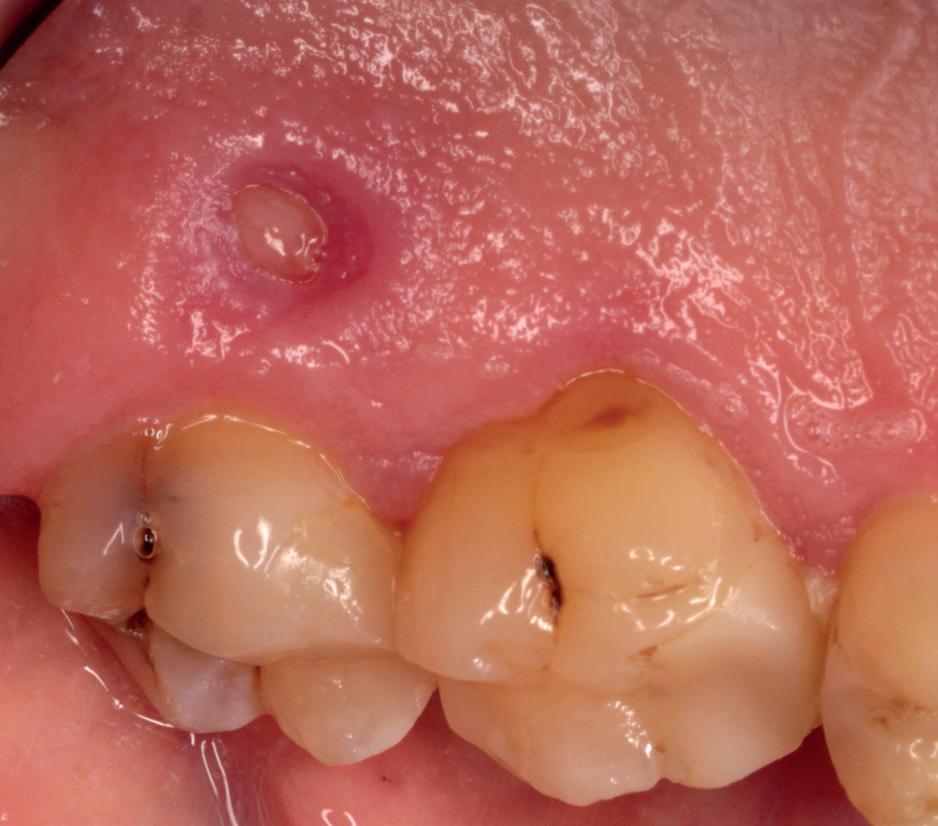

Rondom een implantologietraject zijn vele type behandelingen mogelijk. Implantaatplaatsing, al dan niet gecombineerd met een extractie (immediate-placement), botbreedteherstel, sinuslifting, weke-delenchirurgie (tandvleestransplantatie) of pre-implantologisch botherstel. Met name de grootte van de chirurgische opklap en de behandelduur bepalen de mate van napijn.9,10,11 Bij implantaatplaatsing zonder botherstel is de te verwachten napijn

minimaal. Hetzelfde geldt voor de zogenaamde immediate-placement procedure waarbij het tandvlees niet wordt opgeklapt. Bij weke-delen chirurgie, zoals het aanbrengen van een bindweefselgraft, geeft de donorplaats (veelal palatum/tuber) de meeste nabezwaren.

Afbeelding 1 en 2. Een immediate placement (afbeelding 1) is maar weinig invasief en zal weinig nalast geven. Bij een uitgebreide botopbouw (afbeelding 2) daarentegen is de wond veel groter en kan er meer nalast verwacht worden.

Bij uitgebreidere behandelingen zoals botbreedteen/of hoogteherstel is er vaak sprake van een groter chirurgisch gebied. De mucosa en het botvlies (periost) worden verder afgeschoven en vaak is het noodzakelijk om het rijkelijk doorbloede periost in te snijden (klieven) om de mucosa weer spanningsvrij te kunnen hechten na de ingreep. Dit heeft meer bloeding en zwelling tot gevolg, hetgeen weer meer druk geeft op het wondgebied. Ook de patiënt zelf is